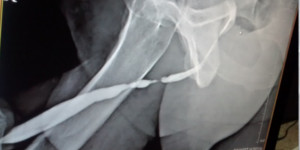

• X-ray studies, Ascending urethrogram.

• This test involves placing a fine catheter into the urethral opening and injecting contrast media .The narrowed segment and the length of narrowed segment can be visualized.